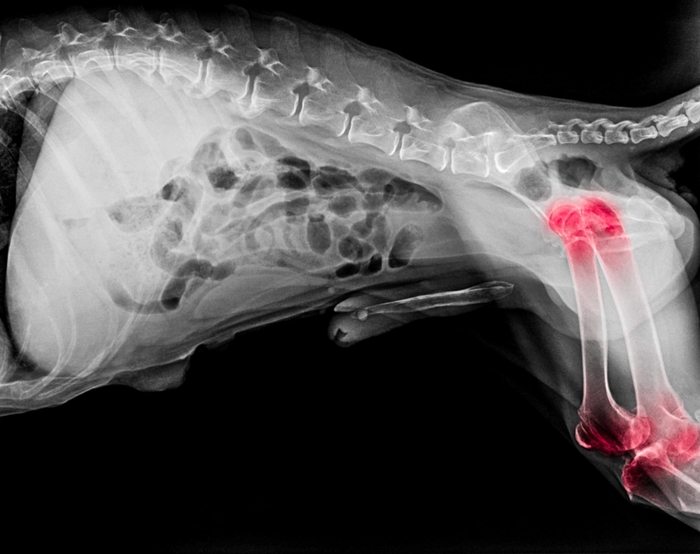

骨も筋肉も丈夫になる

生肉に含まれる食物酵素は、新陳代謝をよくする働きがあるので、余分な脂肪も付かず、骨も筋肉も丈夫になります。